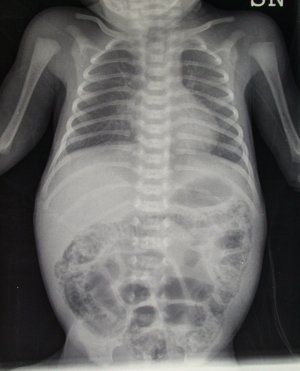

Emma � una bambina nata a 33 settimane di et� gestazionale da taglio cesareo d'urgenza. A 5 giorni di vita ha sviluppato una clinica caratterizzata da feci ematiche, addome globoso e dolente, con anse disegnate e palpabili. La radiografia dell'addome ha dimostrato una marcata pneumatosi intestinale (Figura 1), quadro radiologico suggestivo di enterocolite necrotizzante. Veniva sospesa l'alimentazione per bocca, avviata triplice terapia antibiotica (Ampicillina, Netilmicina, Metronidazolo) e farmaci inotropi (dopamina, dobutamina, plasma). Nonostante il quadro radiologico cos� eclatante la piccola ha ben risposto alla terapia conservativa, non necessitando di intervento chirurgico.

Tre sono i quadri radiologici caratteristici di enterocolite necrotizzante: pneumatosi intestinale (Figura 1), presenza di gas nella vena porta, e pneumoperitoneo con falce d'aria subdiaframmatica in ortostatismo (Figura 2).

Figura 1